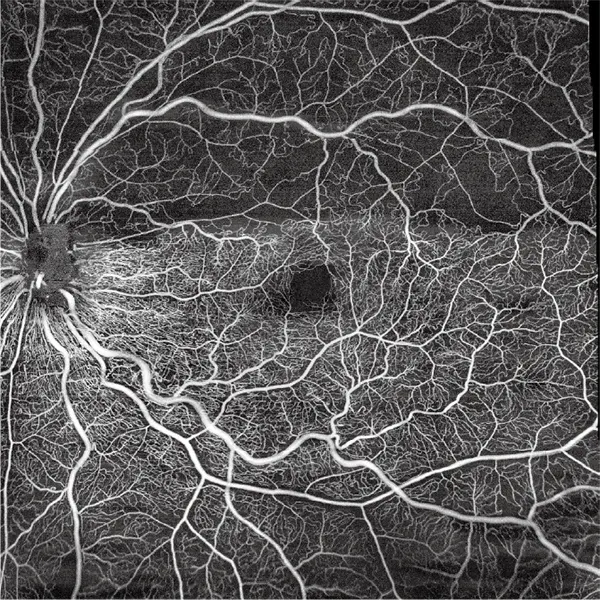

Galería OCTs del TowardPi Yalkaid